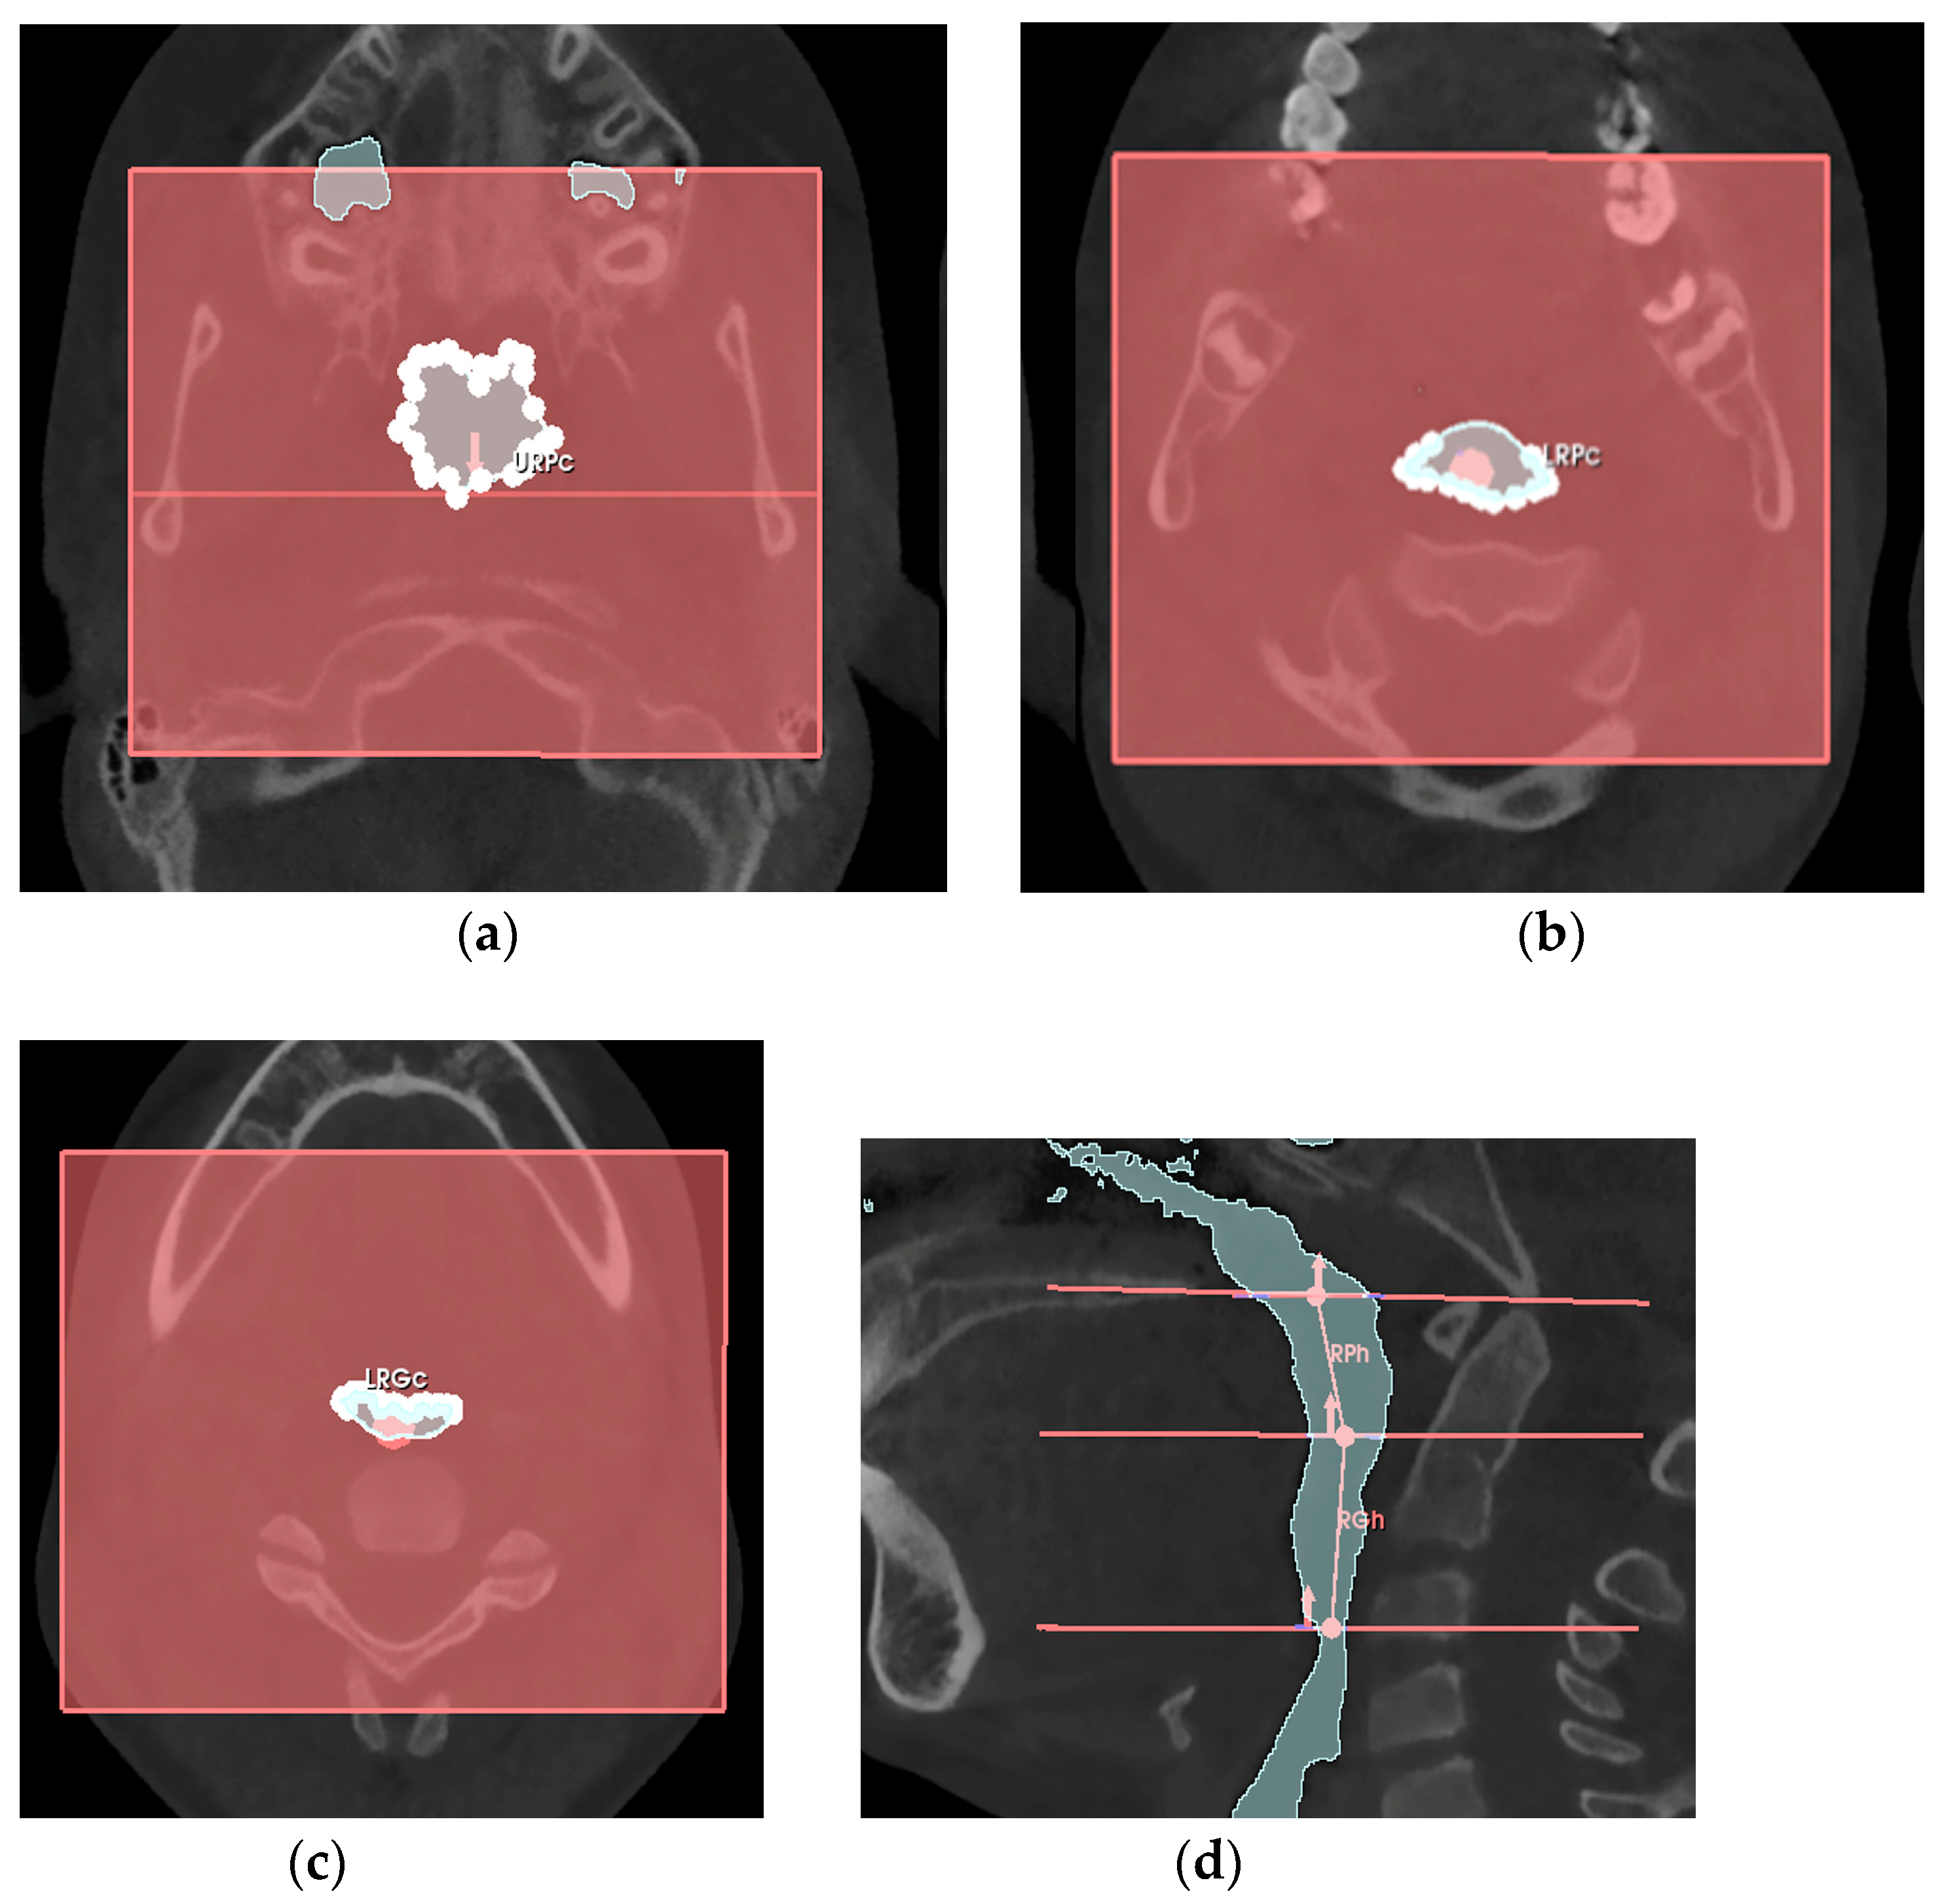

2.5. Volumetric Measurement Protocol

2.6. Airflow Velocity Calculation Protocol

- -

- the retro-palatal volume section was modeled as a right truncated cone, F, with an upper circumference URPc (from which the diameter URPd = URPc/π was derived), a lower circumference LRPc (from which the diameter LRPd = LRPc/π was derived), and a height RPh;

- the retro-glossal volume section was modeled as a right truncated cone, G, with an upper circumference LRPc (from which the diameter LRPd = LRPc/π was derived), a lower circumference LRGc (from which the diameter LRGd = LRGc/π was derived), and a height RGh.

| Variable | Definition |

|---|---|

| URPc (mm) | Upper circumference of the retro-palatal volume, measured on the axial slice where the Ba-PNS plane superiorly defines the retro-palatal volume. |

| LRPc (mm) | Lower circumference of the retro-palatal volume, measured on the axial slice where the horizontal plane of the soft palate inferiorly defines the retro-palatal volume and superiorly defines the retro-glossal volume. |

| LRGc (mm) | Lower circumference of the retro-glossal volume, measured on the axial slice where the horizontal plane of the epiglottis inferiorly defines the retro-glossal volume. |

| RPh (mm) | Height of the retro-palatal volume, the distance measured on the median sagittal slice of the retro-palatal volume from the midpoint of the upper limit defined by the Ba-PNS plane to the midpoint of the lower limit defined by the horizontal plane of the soft palate. |

| RGh (mm) | Height of the retro-glossal volume, the distance measured on the median sagittal slice of the retro-glossal volume from the midpoint of the upper limit defined by the horizontal plane of the soft palate to the midpoint of the lower limit defined by the horizontal plane of the epiglottis. |